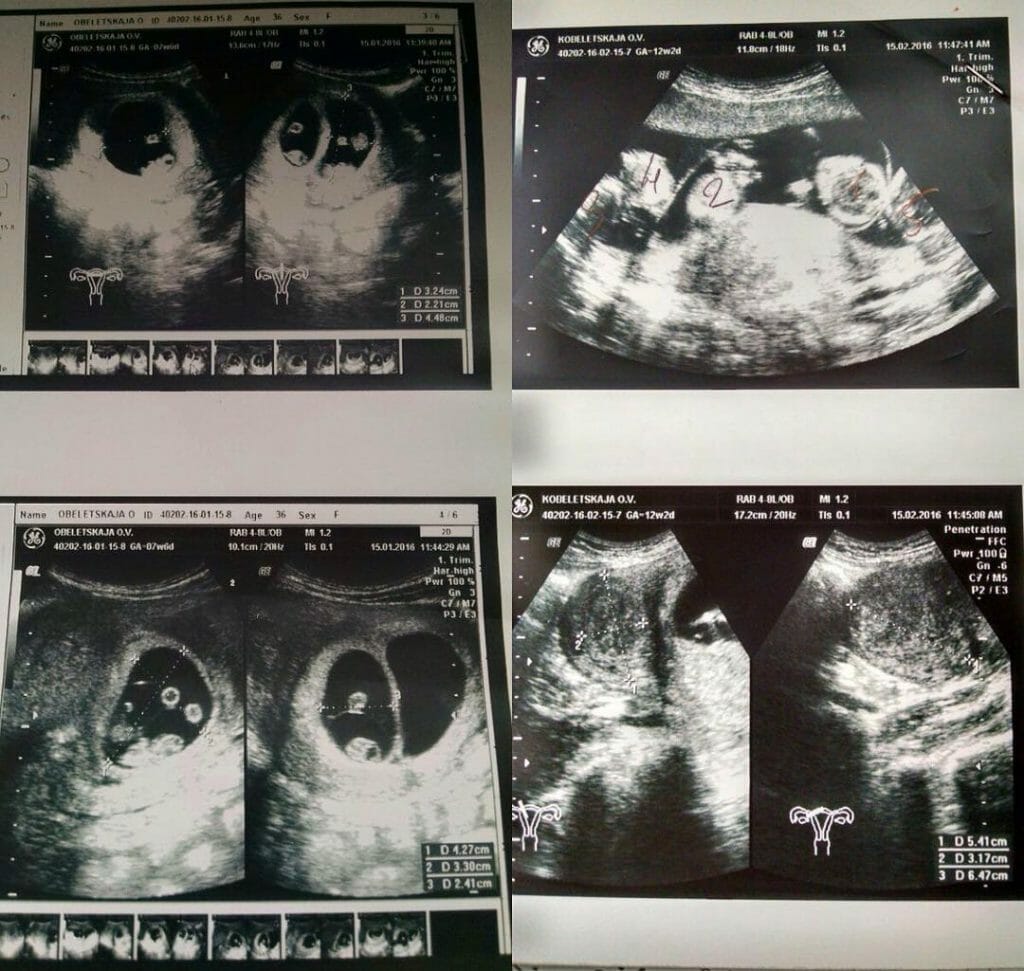

Allting pekade på att hon väntade tvillingar.

Men det läkarna upptäckte på ultraljudet fick mammans hjärta att frysa till is.

Men under hennes ultraljuds fick hon uppleva skräckkänslor på riktigt – när hon såg det chockade uttrycket på doktorns ansikte.

Läkaren sa: ”Jag kan tydligt se fem foster, kanske sex. Det är svårt att säga”.

Det visade i att mamma av en snart skulle bli en sexbarnsmamma – hon var nämligen gravid med femlingar.

”Jag är väldigt chockad, för att jag trodde att jag väntade tvillingar eller något liknande”, sa mamman.

Femlingar är extremt sällsynta, det förekommer bara en gång på cirka 50 miljoner graviditeter.